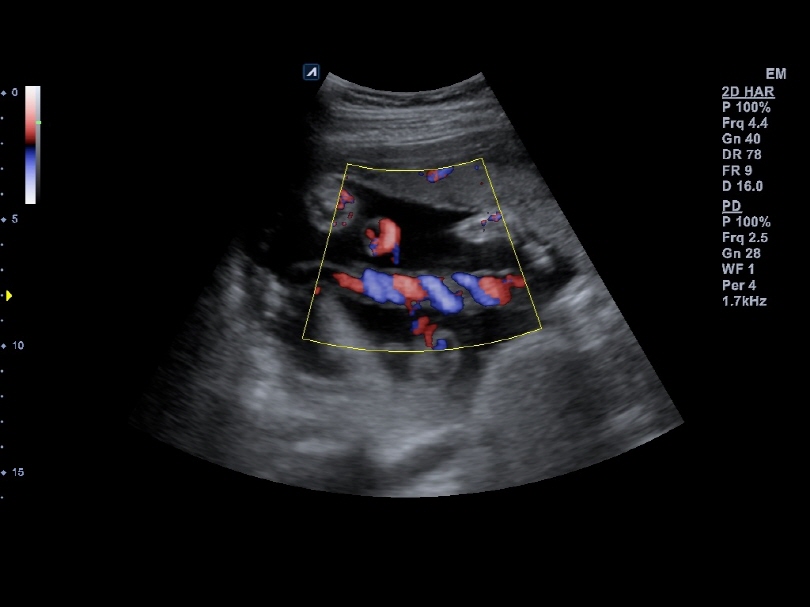

C1-6CT

C-Architecture (PowerView™)

Convex transducer (1-6MHz)

Application:

Abdomen, EM, Gynecology, Obstetrics